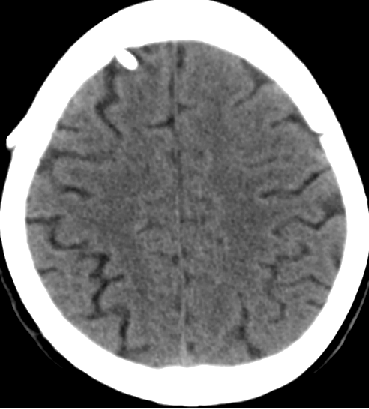

2014-10-17 CT

仍时有前额部疼痛,程度轻,调压190—200